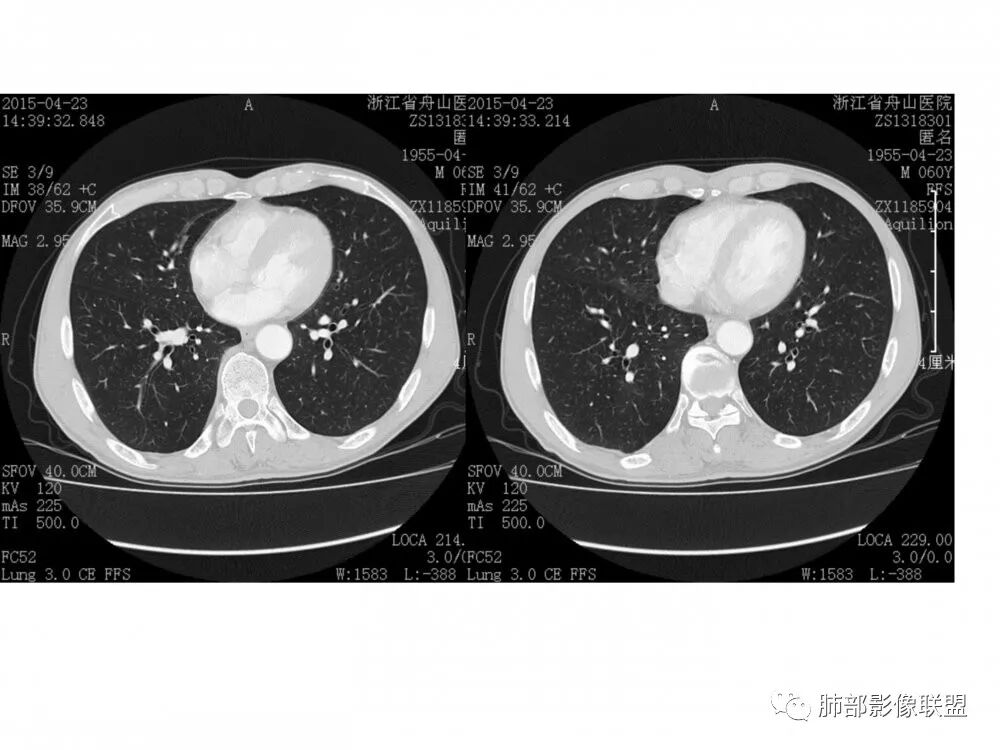

右肺下叶支气管开口新生物,轴位管腔及纵向基底干大部分受累狭窄,支气管管壁破坏明显,强化较低不均匀,肺门、7组、4R淋巴结肿大,考虑恶性支气管腔内肿瘤,鳞癌可能性大,需要与类癌、涎腺类肿瘤鉴别

老年男性,60岁,右下肺门肿块,右下支气管粘膜下生长,并堵塞,无明显阻塞性肺炎和肺不张,早期多发淋巴结转移,似不均匀强化。综合看恶性程度高,考虑大细胞癌,一个不支持点,大细胞癌外周多见。

优先需要与小细胞癌鉴别,再鳞癌鉴别。肿瘤恶性程度排序,小大腺鳞类。小细胞癌不支持点是:1.沿着支气管粘膜下生长,支气管阻塞轻,爬行征;2.包绕血管,冰冻纵隔,有可能病灶比较小,所以没那么快包裹;这例这点不符合。其他倒是符合中央型小细胞癌,比如转移早,恶性程度高。

男,60岁,右肺下叶支气管开口新生物,轴位管腔及纵向基底干大部分受累狭窄,支气管管壁破坏并突破形成腔外肿块,强化较低不均匀,右肺门、7组、4R淋巴结肿大,考虑恶性没问题,鳞癌可能性大,类癌、粘液表皮样癌,乳头状瘤待排。

右肺下叶支气管不规则软组织肿块,病灶沿支气管生长,有一定的张力,部分包绕支气管壁,增强病灶内可见中度强化,内部有延迟强化的特点,周围淋巴结增大,诊断恶性病变无疑,远端无明显支气管阻塞,主要考虑粘液表皮癌,腺样囊腺癌,鳞癌之间鉴别,病灶有类似神经源性病变生长方式,腺样囊腺癌,其次考虑鳞癌或粘液表皮癌。